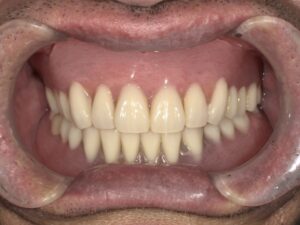

装着してもらった状態です

安定感が非常に高く、本人曰く

『ほとんどの物は咬める』とのことでした。

個人差はあると思いますが、

おせんべいも問題なく咬めるそうです。